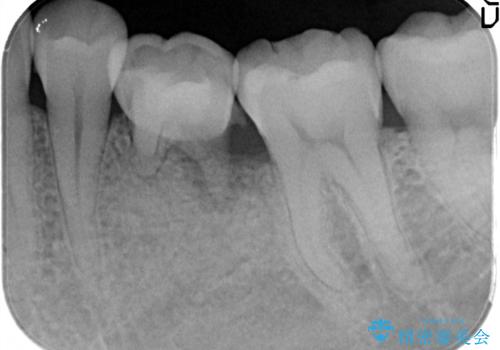

奥歯が痛い。乳歯を抜歯し、ブリッジによる咬合回復。

- 晩期残存した乳歯が痛くなったことを主訴に来院されました。

歯周病が進行していたため、抜歯を行い咬合回復を行いました。

インプラントは希望されなかったため、ブリッジにて治療を行っております。